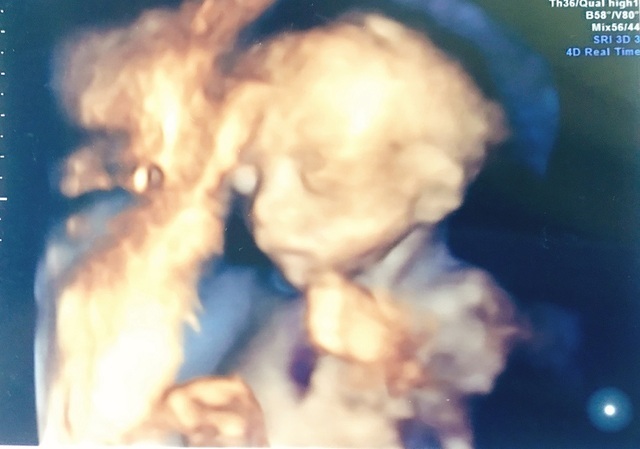

21週0日(21w0d・男の子)|Erimak さん(32歳)

エコー写真撮影時のエピソード:

もぞもぞと胎動が分かり始めしゃっくりもよくしていました!4Dをしてお顔を見せてくれた日でした。

もぞもぞとよく動き疲れたのか大きなあくびをした瞬間のエコー写真です。 お顔を見せてくれた感動とあくびをしている神秘的な姿にも感動した日でした